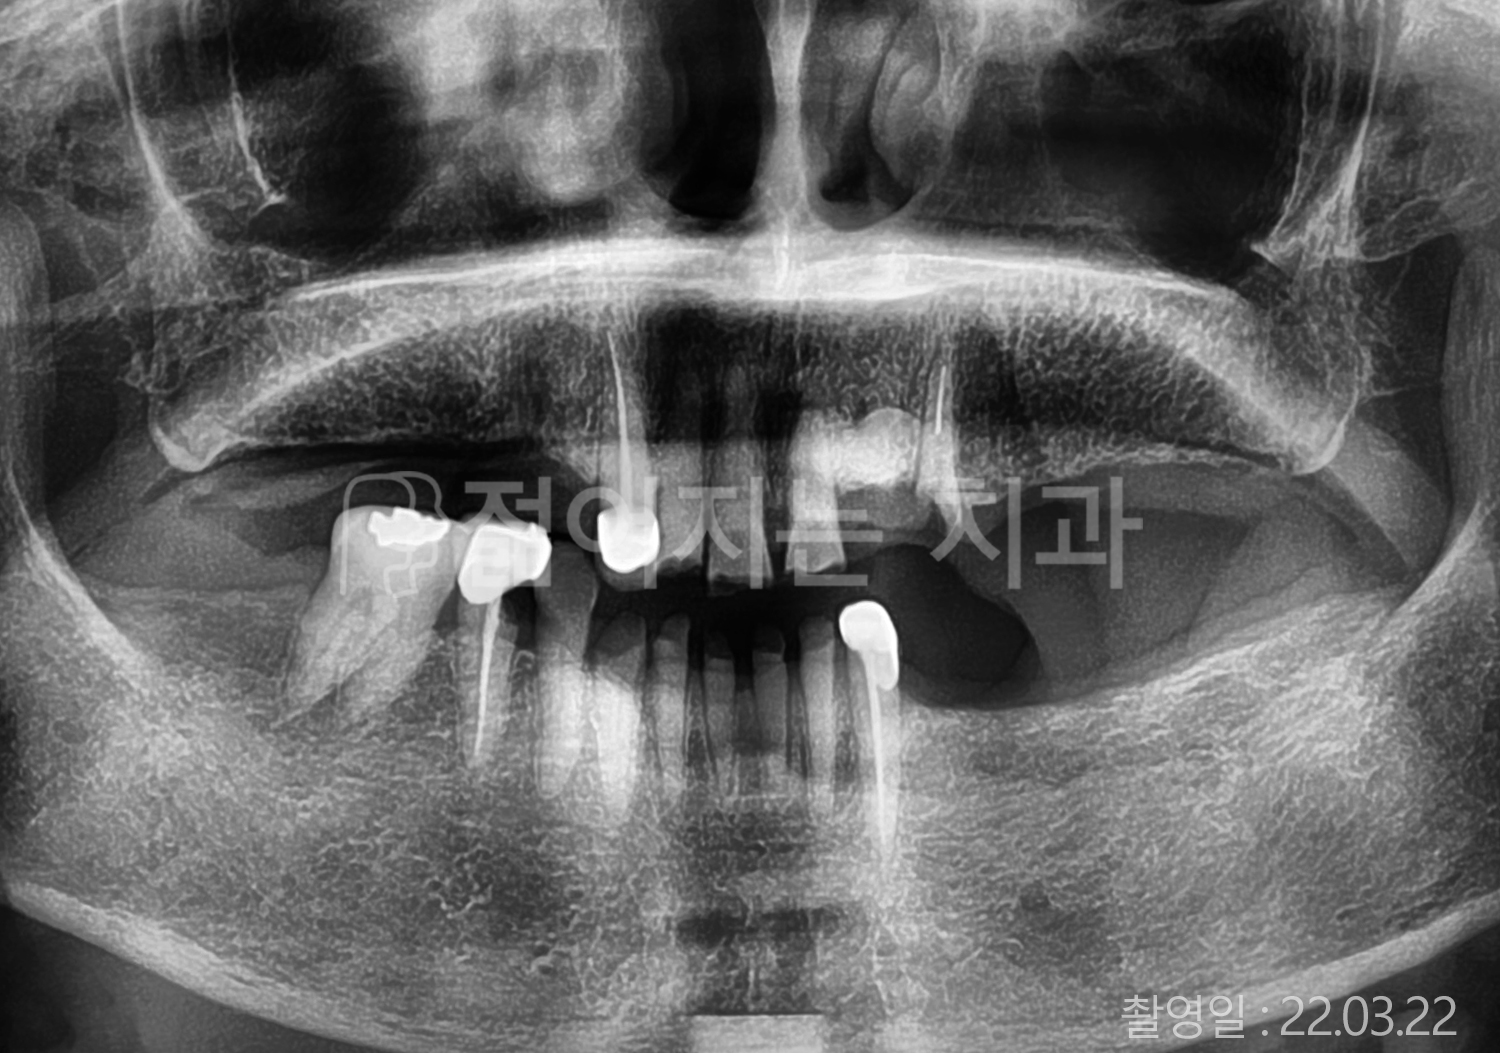

• 60대 전체치아 10개 이상 임플란트